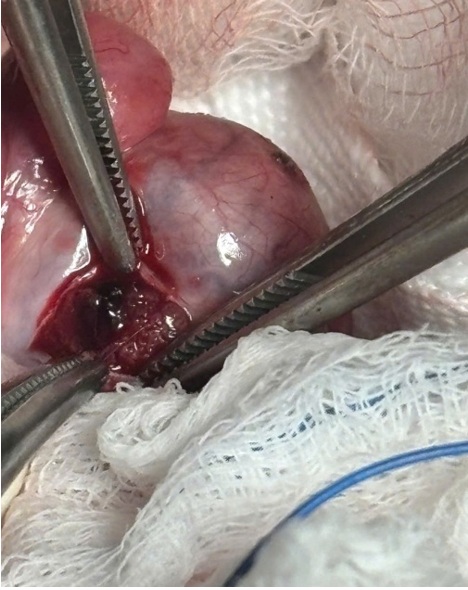

Trong quá trình phẫu thuật:

• Bìu trái được mở để bộc lộ tinh hoàn

• Phát hiện tổn thương tại cực trên tinh hoàn trái

• Tiến hành mở nhu mô tinh hoàn tại vị trí tổn thương

• Lấy ra một mảnh kim loại kích thước khoảng 3 mm nằm trong tinh hoàn

Sau khi lấy dị vật, nhu mô tinh hoàn được cầm máu và khâu phục hồi. Ca phẫu thuật diễn ra thuận lợi và dị vật được lấy ra hoàn toàn.

Hình 2. Mảnh kim loại được lấy ra từ nhu mô tinh hoàn trong phẫu thuật.